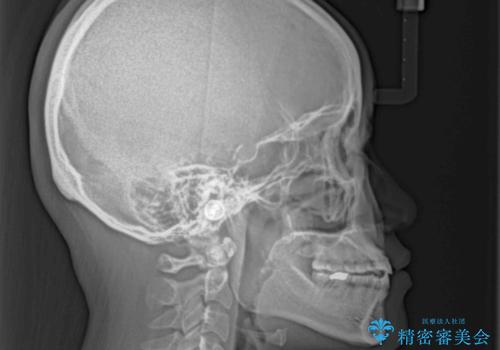

隙間の空いた前歯を治したい インビザライン矯正治療

- 上下の前歯の隙間を気にして来院された患者様です。

インビザラインを用い、上下歯列のスペースを閉じていくこととしました。

治療期間中は奥歯がほとんど咬めない状態が続き、食事に大変苦労されました。

最終的には隙間もしっかりと閉じ、奥歯も咬みやすい状態でしあげることができました。